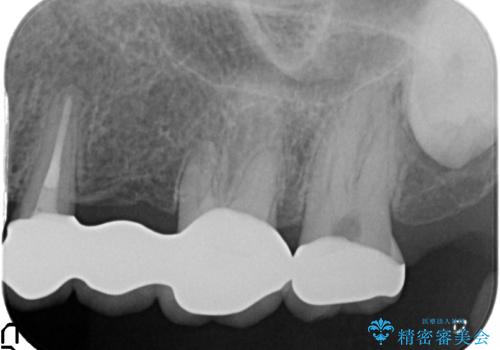

- 20年前に治療した銀歯が壊れ、審美的な修復を希望され来院されました。

銀歯・虫歯を除去し、ジルコニアを咬合再構成を行います。